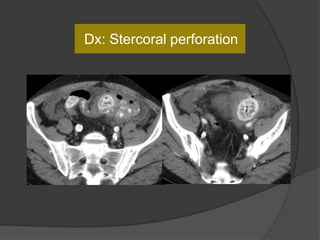

Extraluminal fecal matter in the peritoneal cavity and air loculi

Fecaloma at

the perforation

site

Colon wall thickening due to pressure necrosis

Case 6: 67 F with constipation x 5 d, abdominal

pain and distension

Dx: Stercoral perforation

Stercoral colitis

 Fecal impaction may rarely lead to perforation, colonic obstruction

and fecal peritonitis.

 Fecal impaction results in ischemic pressure necrosis of the rectal

and sigmoid colonic wall leading to stercoral ulcer formation and

subsequently perforation.

 Most common locations :anterior rectum, the antimesenteric border

of the rectosigmoid junction, and the sigmoid colon.

 Mean age 59 yrs. Risk factors : chronic intermittent constipation,

use of nonsteroidal anti-inflammatory drugs, antacids, steroids,

codeine, and heroin.

 Presence of underlying diverticulitis, IBD or obstruction excludes

the diagnosis of primary stercoral perforation.